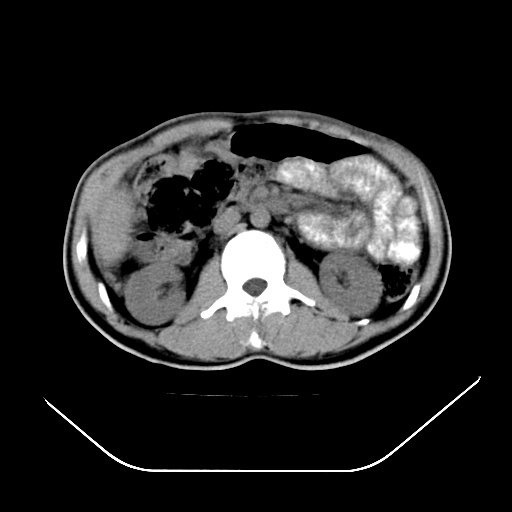

以下是引用文莱在2008-7-17 16:32:00的发言:[br]胆囊结石 余未见异常

以下是引用随光逐影在2008-7-17 17:52:00的发言:[br]1)胆囊结石。2)肝门及胰头区淋巴结肿大可能(原因不明);建议行进一步检查。

以下是引用卜一在2008-7-17 16:37:00的发言:[br]支持胆囊结石!!!至于胰头区病变——建议强化后再定论!